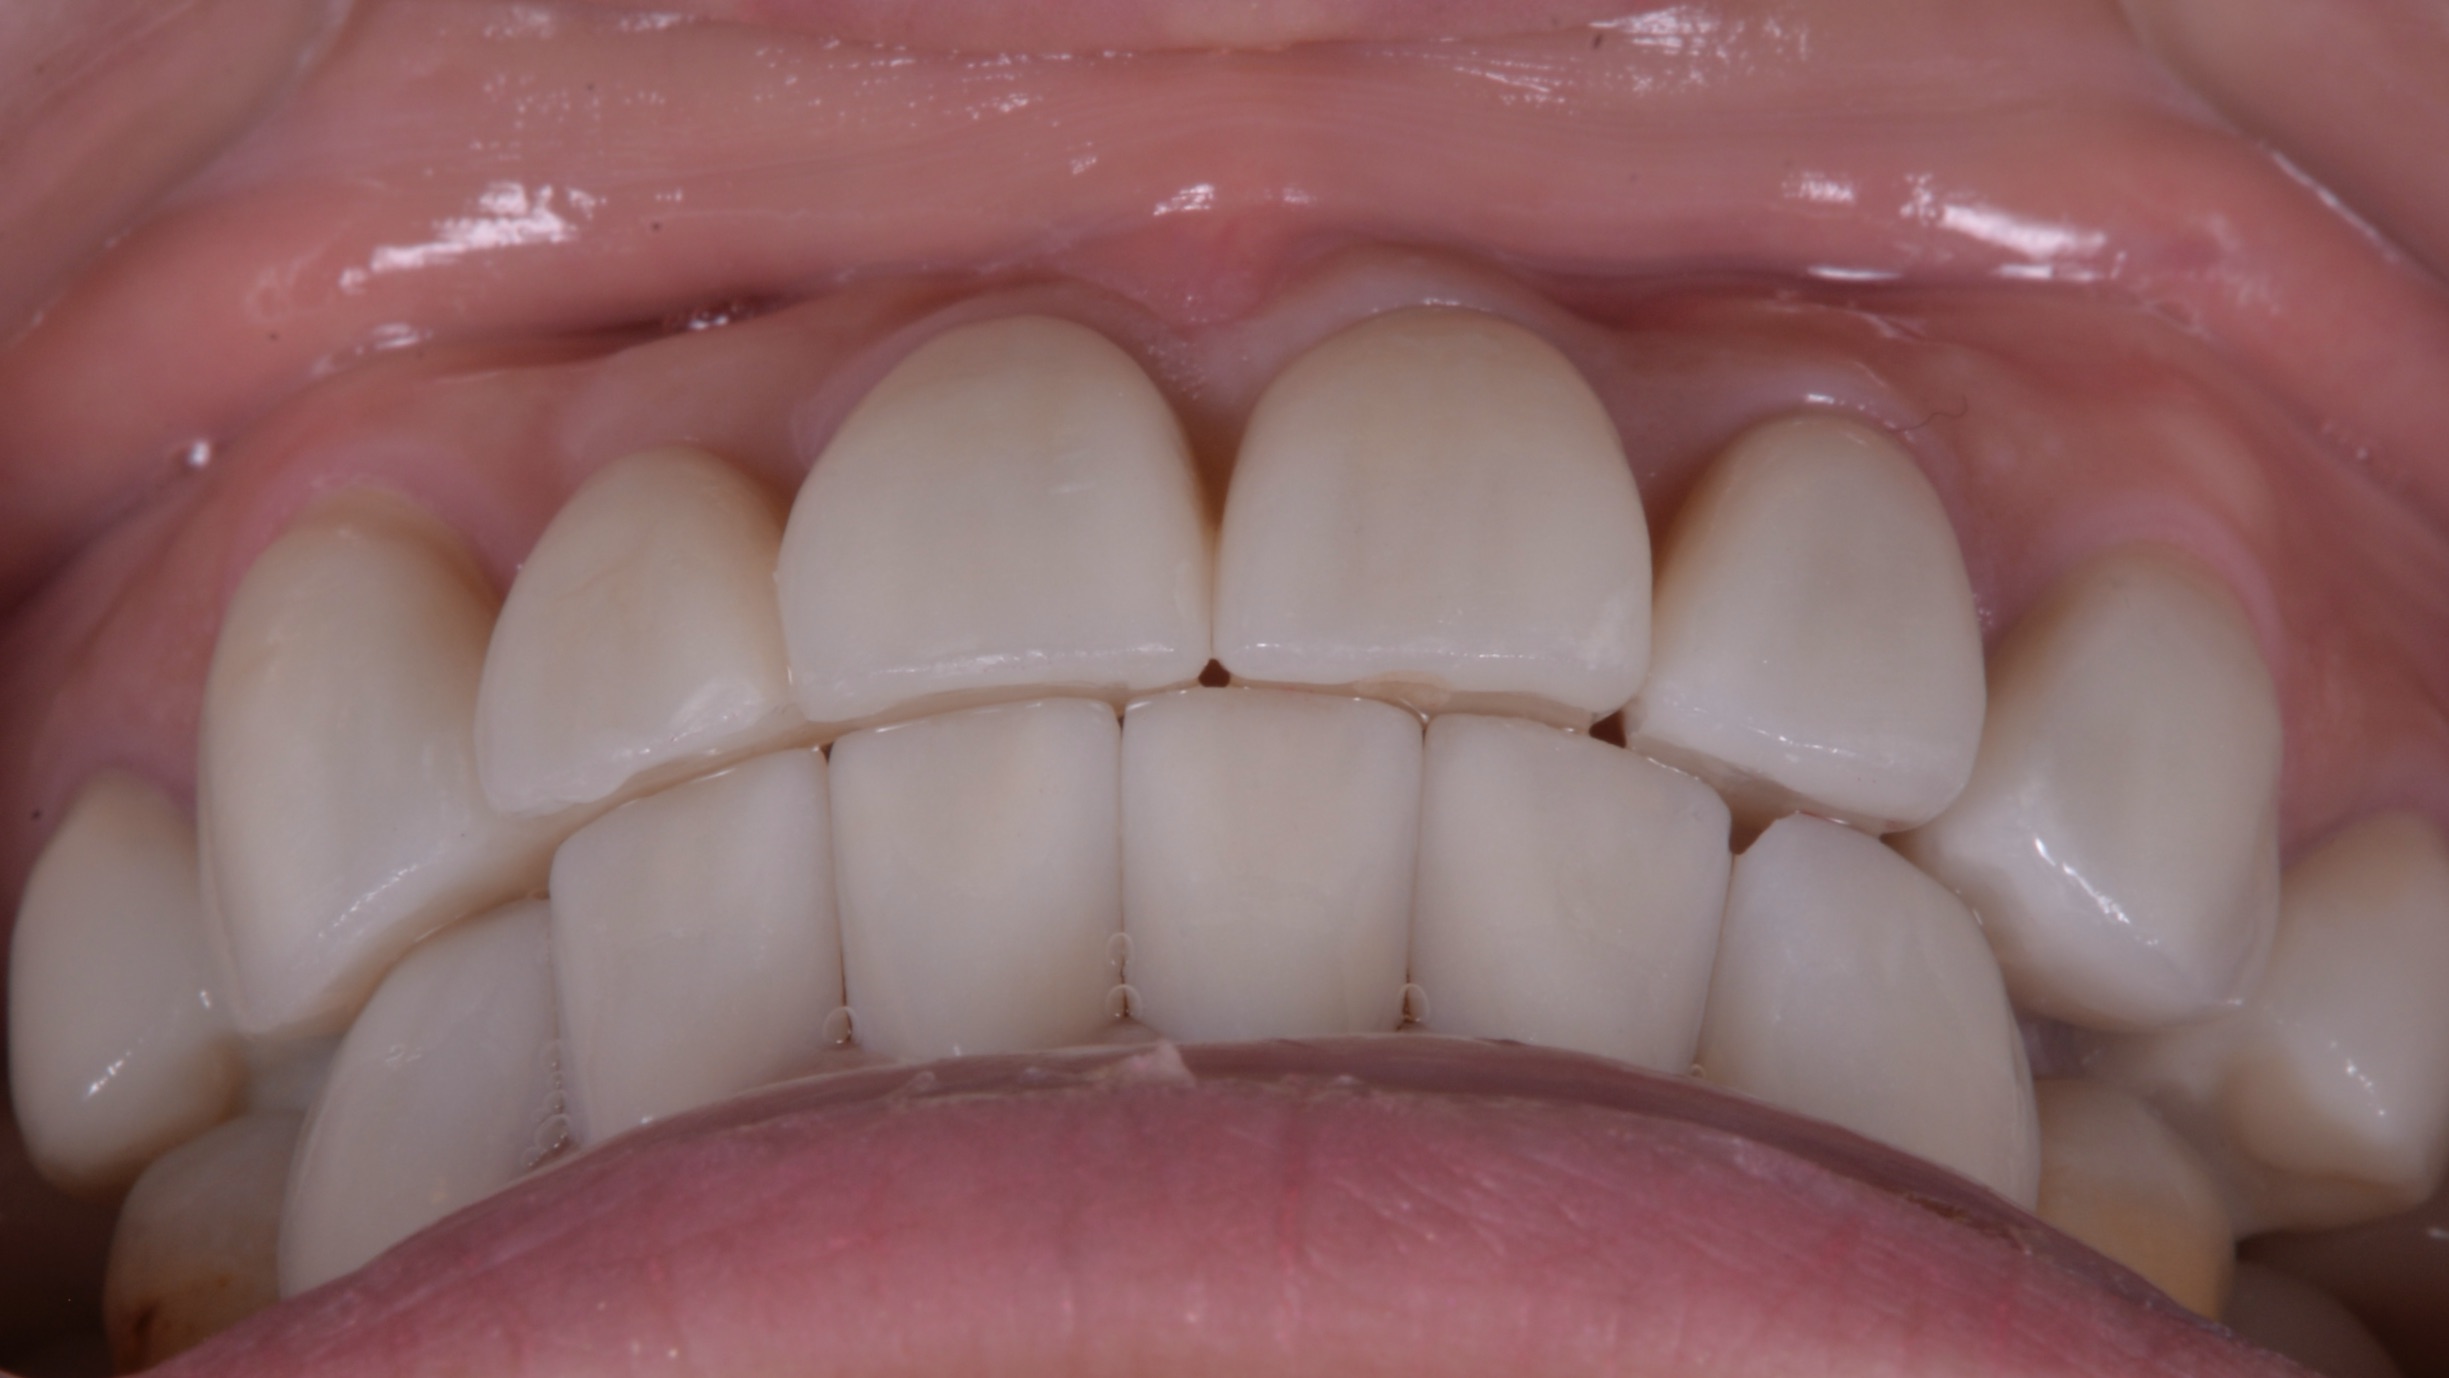

患者自身でもいくどとなく再現ができる適切な噛み合わせのポジションで前歯しっかり噛ませることができました!

変色した歯もセラミックで改善!

前歯のインプラントもどこに入っているかわかりません。